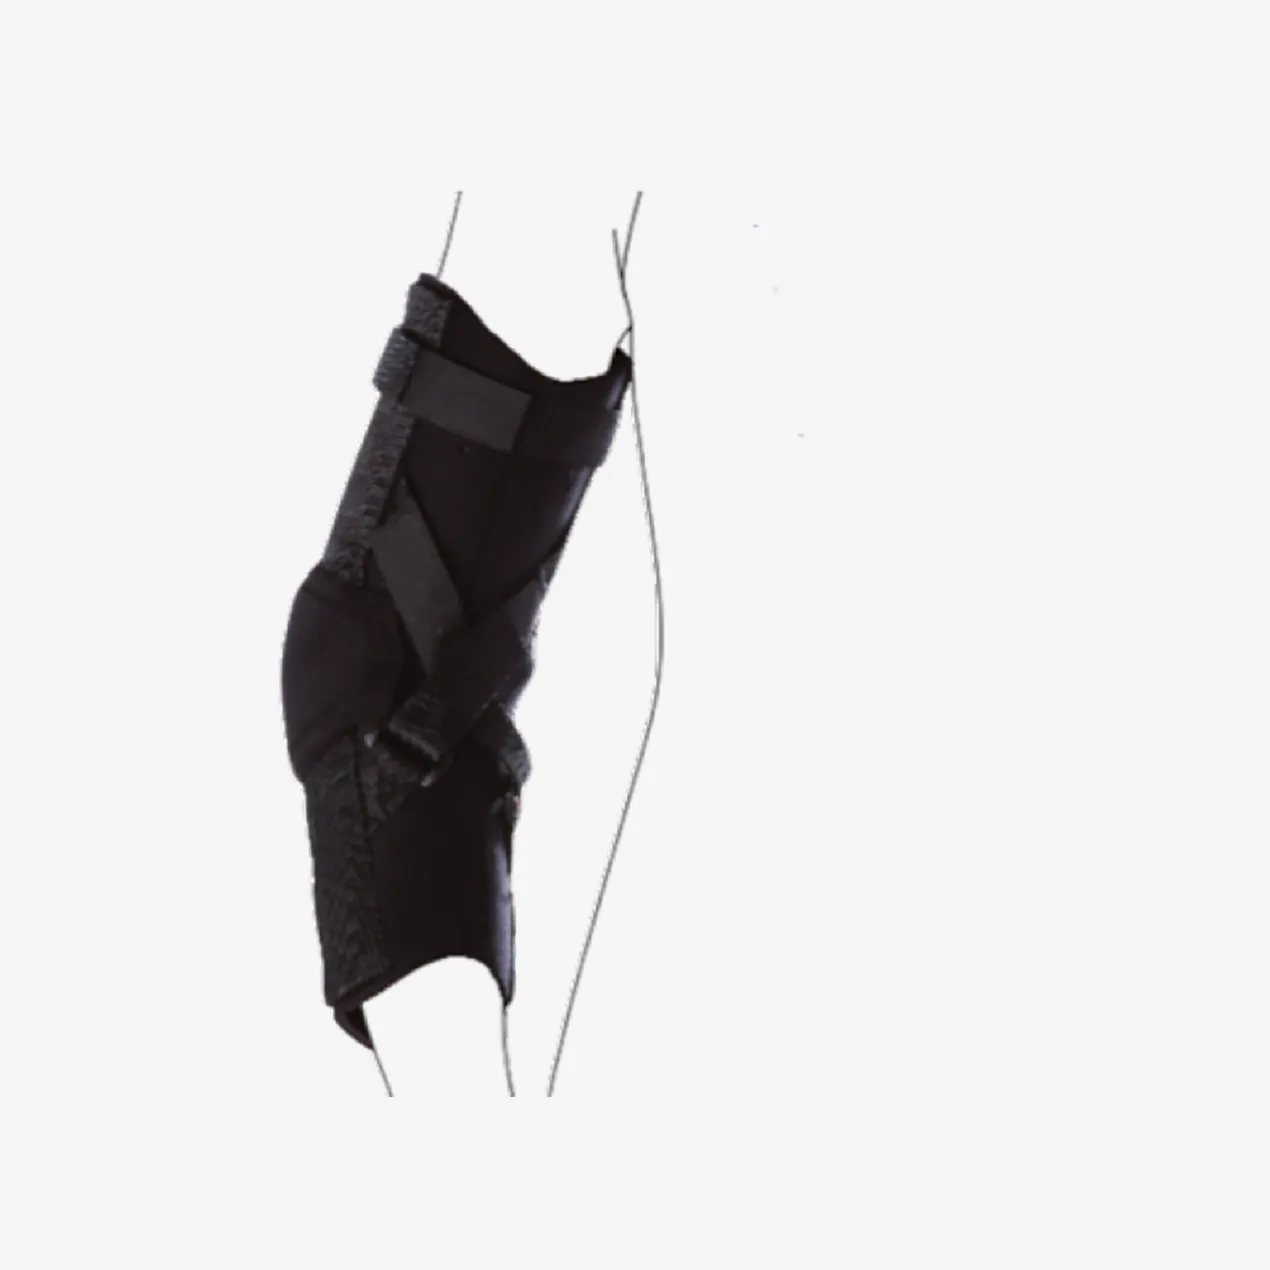

Ulnar Collateral Ligament (UCL) Elbow Brace

دعامة كوع مفصلية مصممة خصيصاً لحماية الكوع الإنسي من إجهاد الأروح، يستخدمها رماة البيسبول ورماة الرمح.